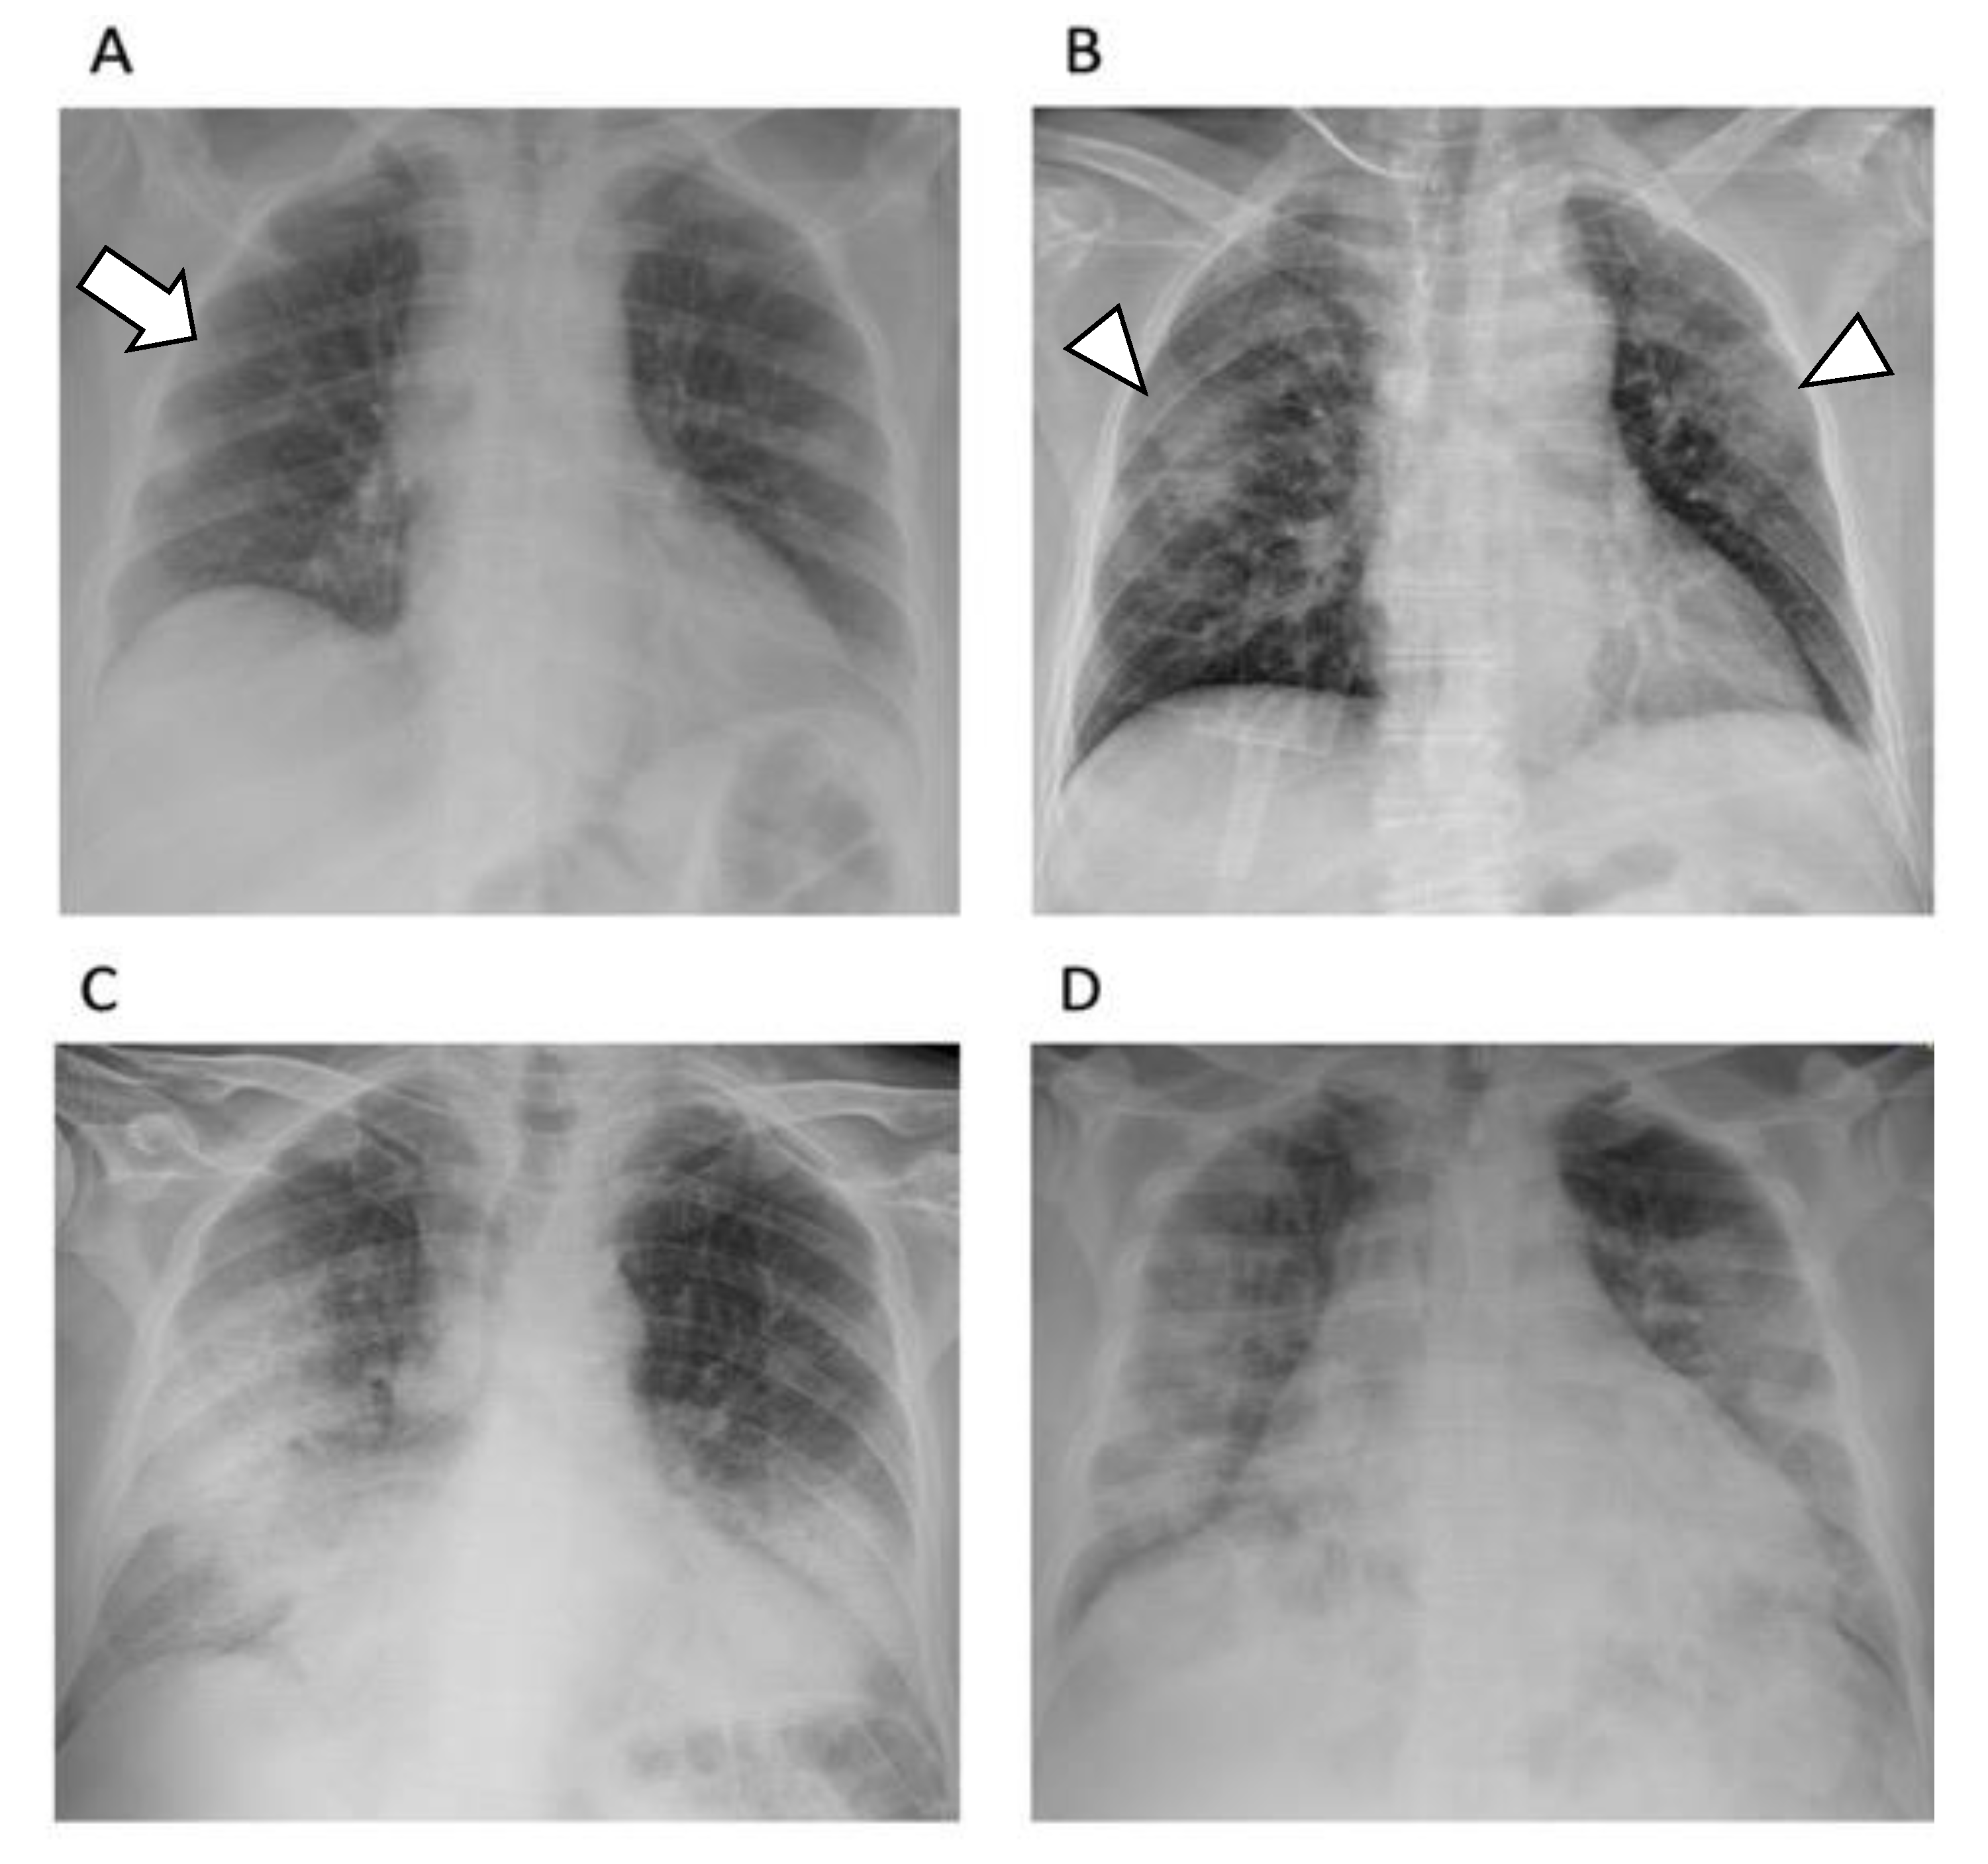

2.6. The Usefulness of Chest X-ray